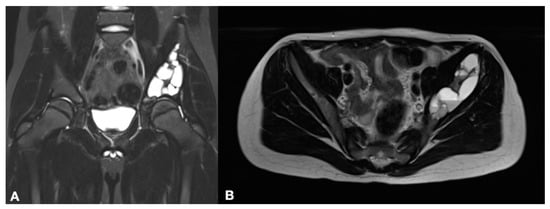

2. Materials and Methods

3. Results